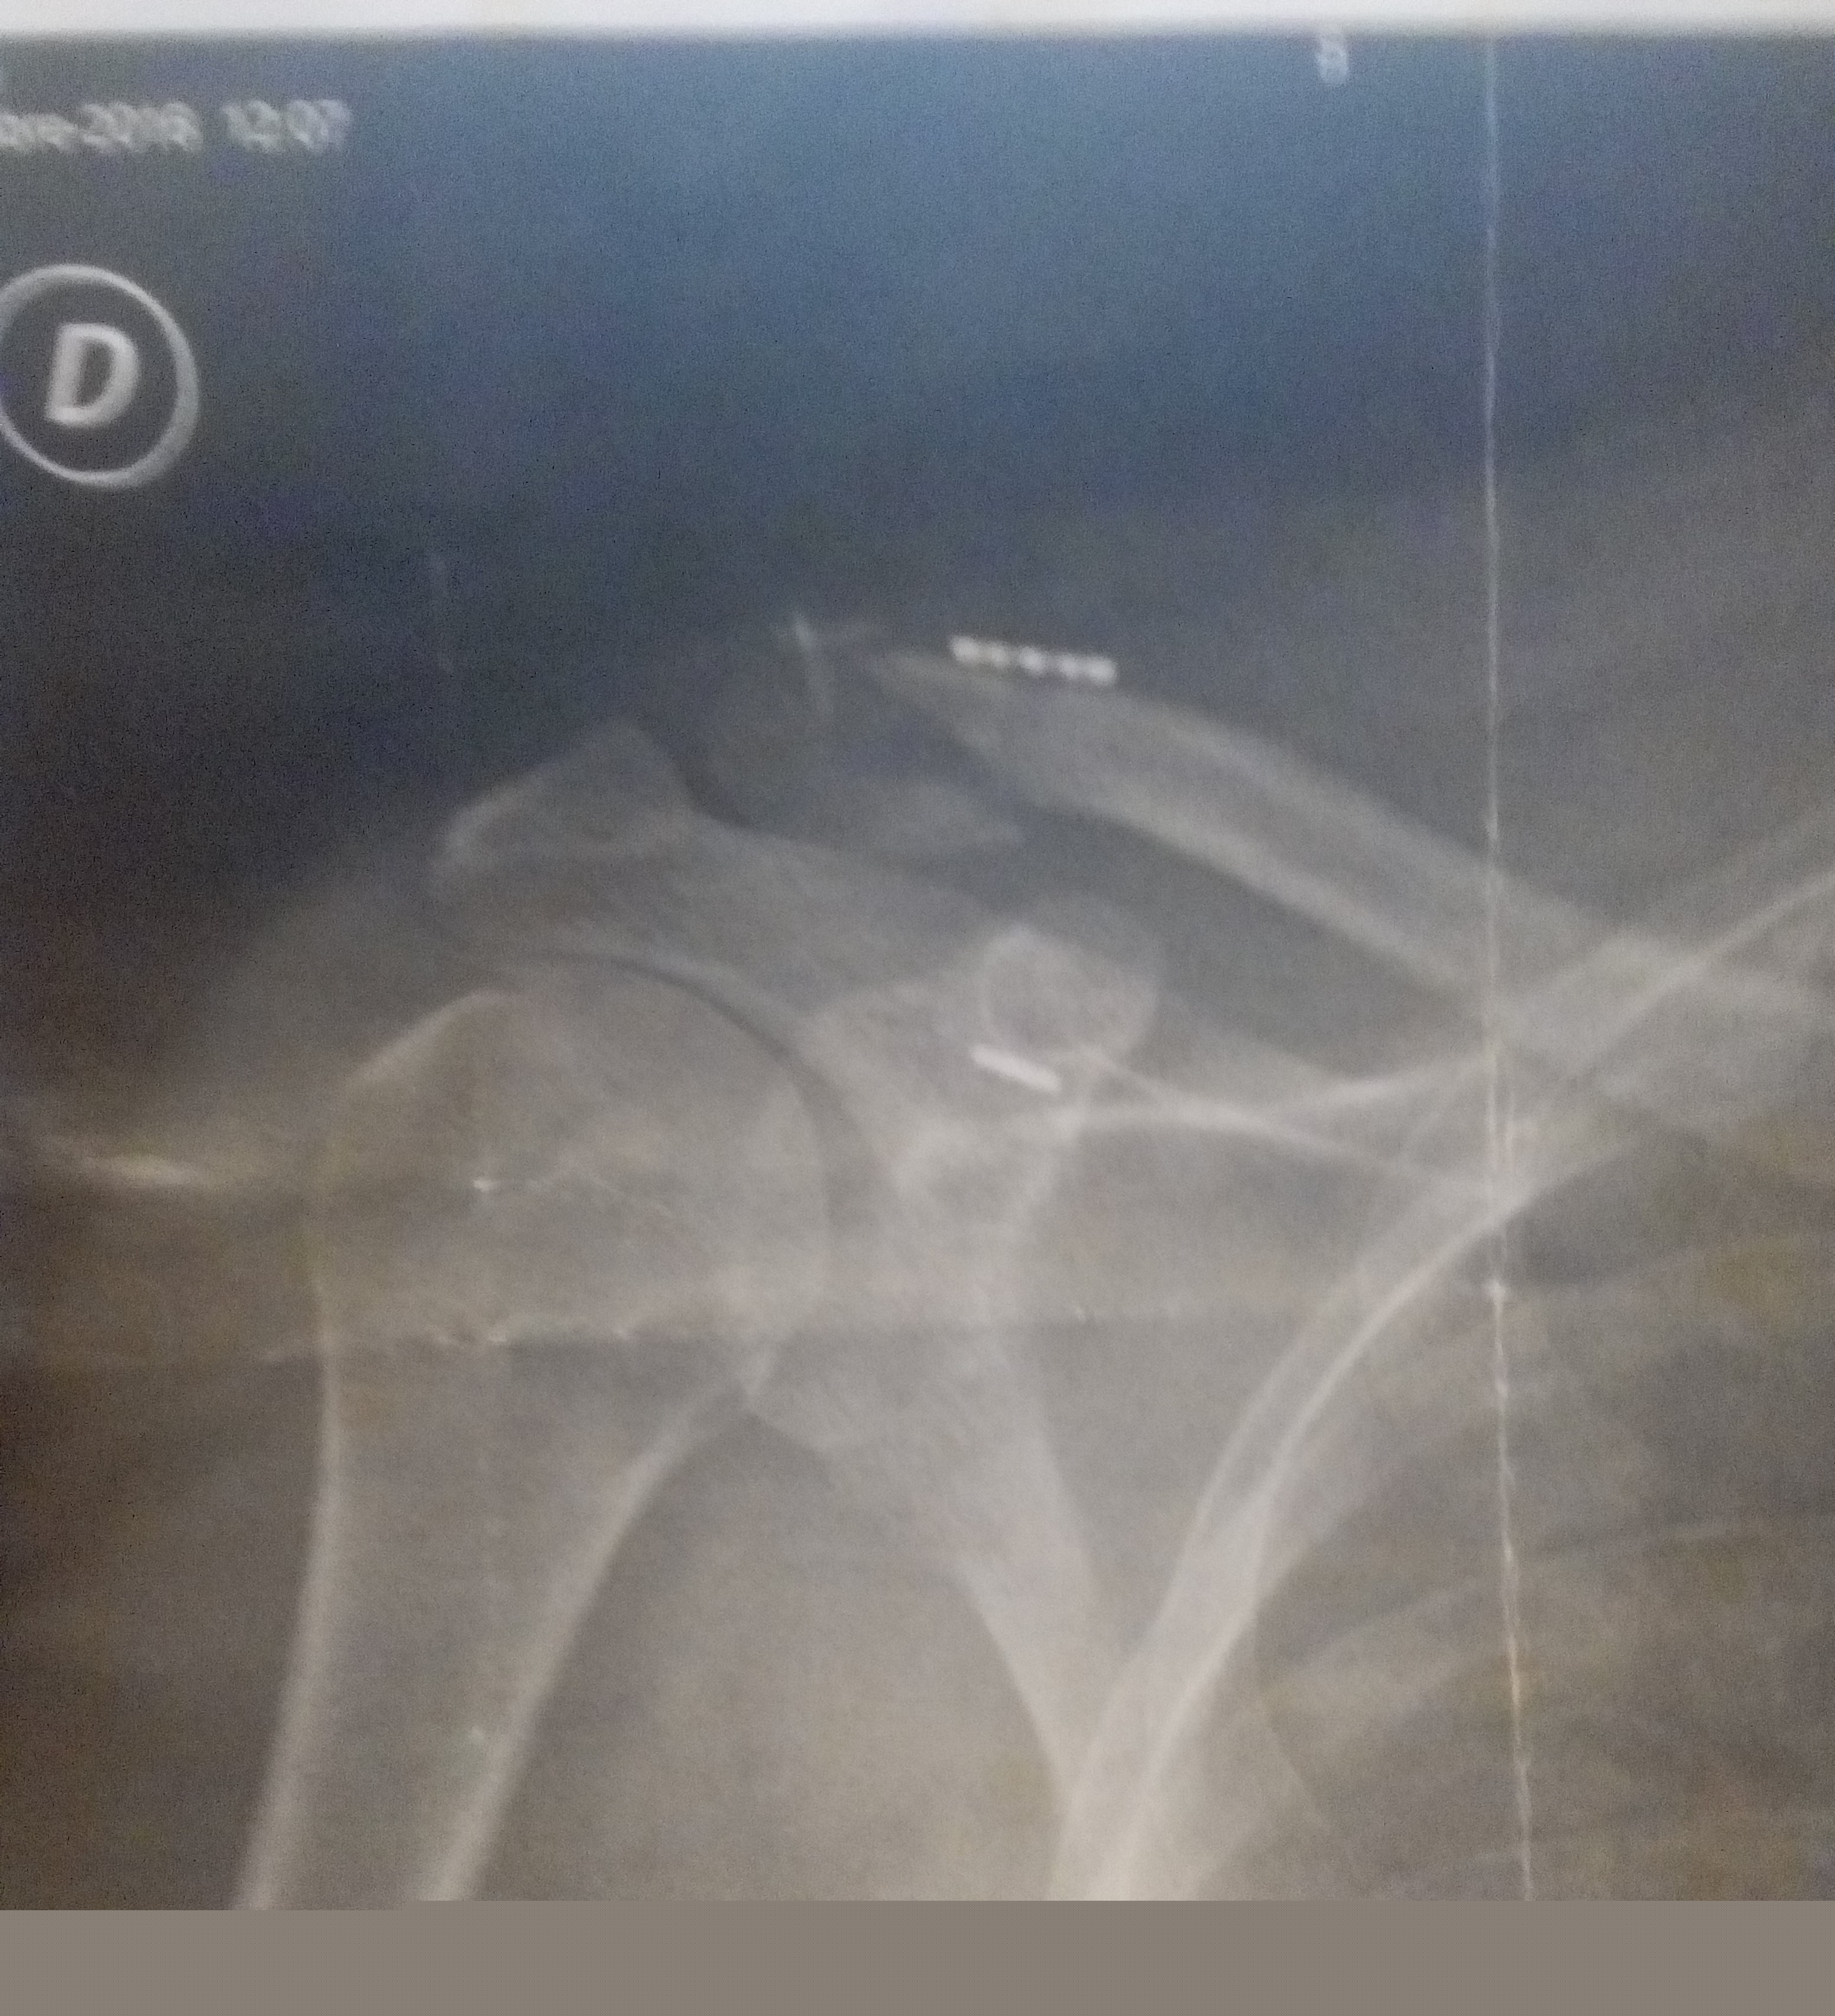

Bilan clavicule droite et pouce gauche fracturé...

Il va bien, il devrait être opéré aujourd'hui...

Les infirmieres prennent bien soin de lui, je suis intervenu pour le casting...juste avant le scanner j'ai dit a l'infirmière qu'il fallait me le remette vite d'aplomb il roulait demain! elle ma répondue ne pas être une magicienne, on savait pas encore ce qu'il avait...c'est parents sont revenus de Narbonne pour l'occasion...